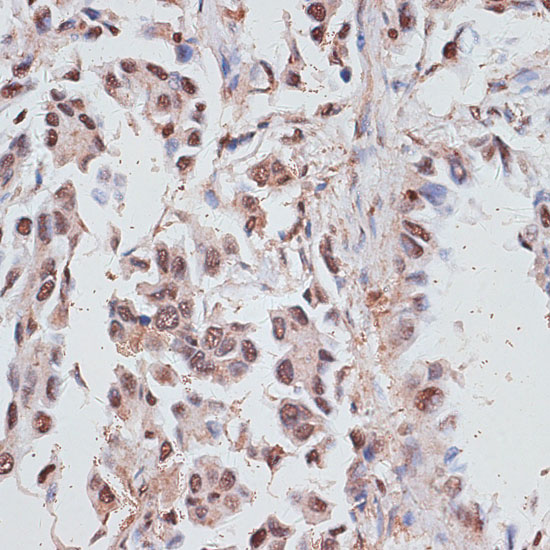

Immunohistochemistry of paraffin-embedded human lung cancer using RPA1 at dilution of 1:100 (40x lens).

Immunohistochemistry of paraffin-embedded human uterus using RPA1 at dilution of 1:100 (40x lens).